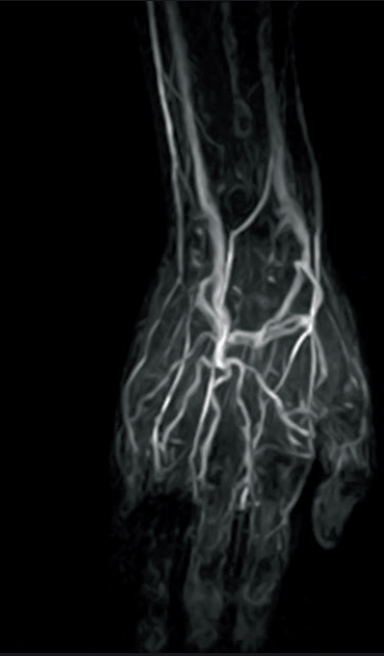

3D-VASC-ASL (Non-Subtraction technique)